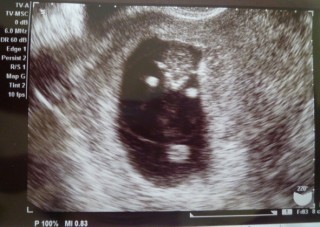

初産で双子ちゃん♪

25mと21mだから若干小さめだけど

元気に動いてくれてました(^-^)/